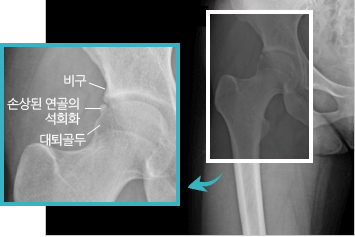

비구 대퇴 충돌 증후군이란?

비정상적인 대퇴 골두나 비구의 변형에 의하여 굴곡 운동시 비구와 대퇴경부가

충돌하면서 통증이 발생하는 질환입니다. 비구순이라는 관절주머니 같은 구조와

관절을 덮고 있는 연골의 손상을 주어 궁극적으로 고관절의 관절염을 유발합니다.